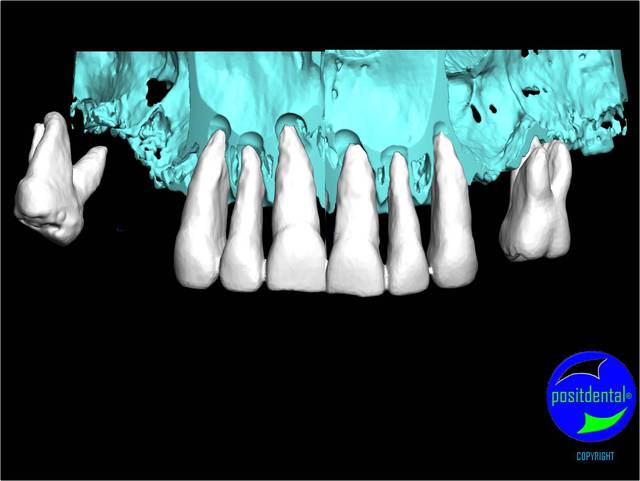

rendu 3D maxillaire sup, pano et photo

3D maxillaire inférieur et photo